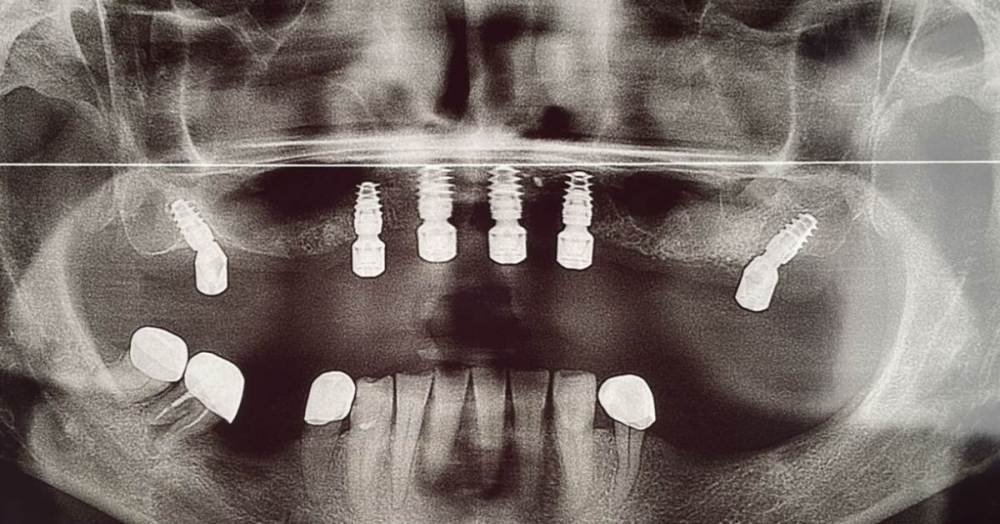

Irouil Опубликовано 1 октября, 2023 Поделиться Опубликовано 1 октября, 2023 Чего-то я не понял - КТ с зубами ещё, а шаблон на беззубую челюсть... Ссылка на комментарий

Большой Зеленый Опубликовано 2 октября, 2023 Автор Поделиться Опубликовано 2 октября, 2023 Зубы удалил предварительно. Толкать импланты в гной нехорошо. Ссылка на комментарий